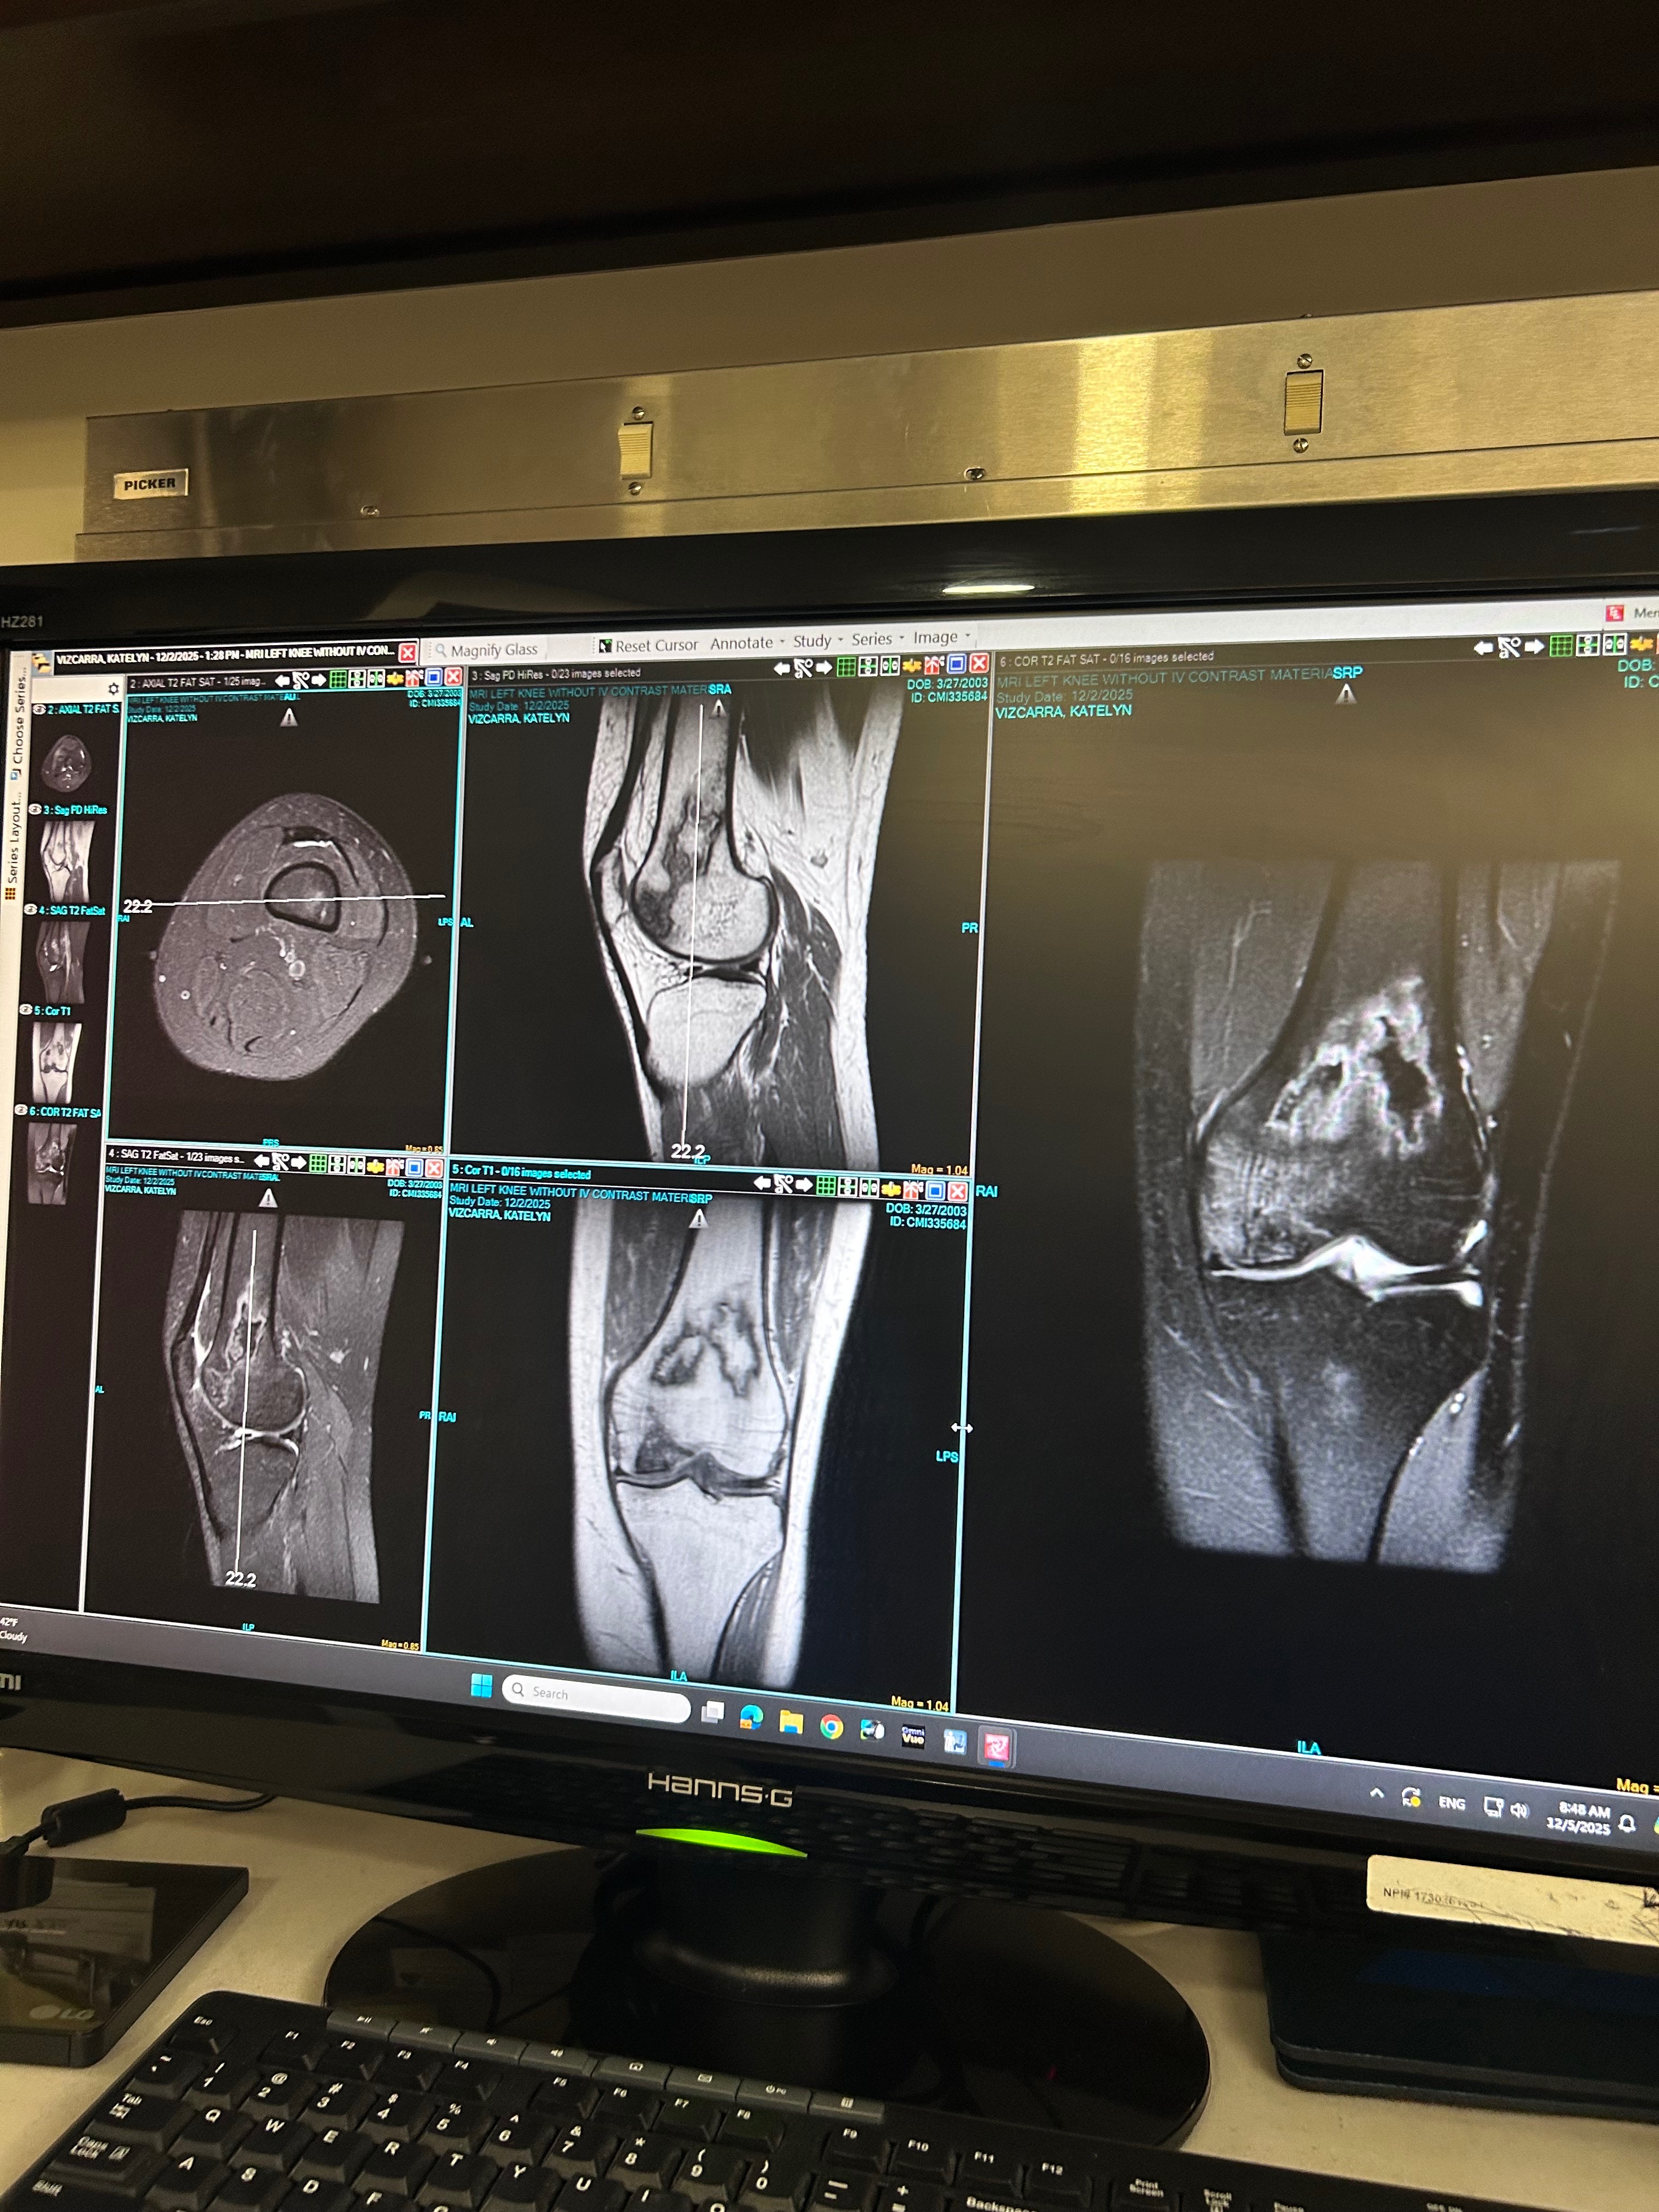

Hi, my name is Katelyn Vizcarra, and asking for help like this is one of the hardest things I’ve ever had to do. Since I was just 12 years old, I’ve been living with SLE (Lupus) and Rheumatoid Arthritis. For years, my life has revolved around doctors, medications, and treatments, all in hopes of feeling better. Sadly, nothing has worked, and many of the medications meant to help me have instead damaged my body. I now suffer from severe stomach issues and vomit every single day. Recently, I was also diagnosed with , Osteochondrosis and the pain has become unbearable. Most nights, I cry myself to sleep because my body simply won’t let me rest. Even so, I choose to show the world a smile. My life may look like rainbows and sunshine, but that’s because I fight every day to be seen as strong—not broken. I don’t want to be known as the sick girl; I want to be known as the strong girl who refuses to give up.